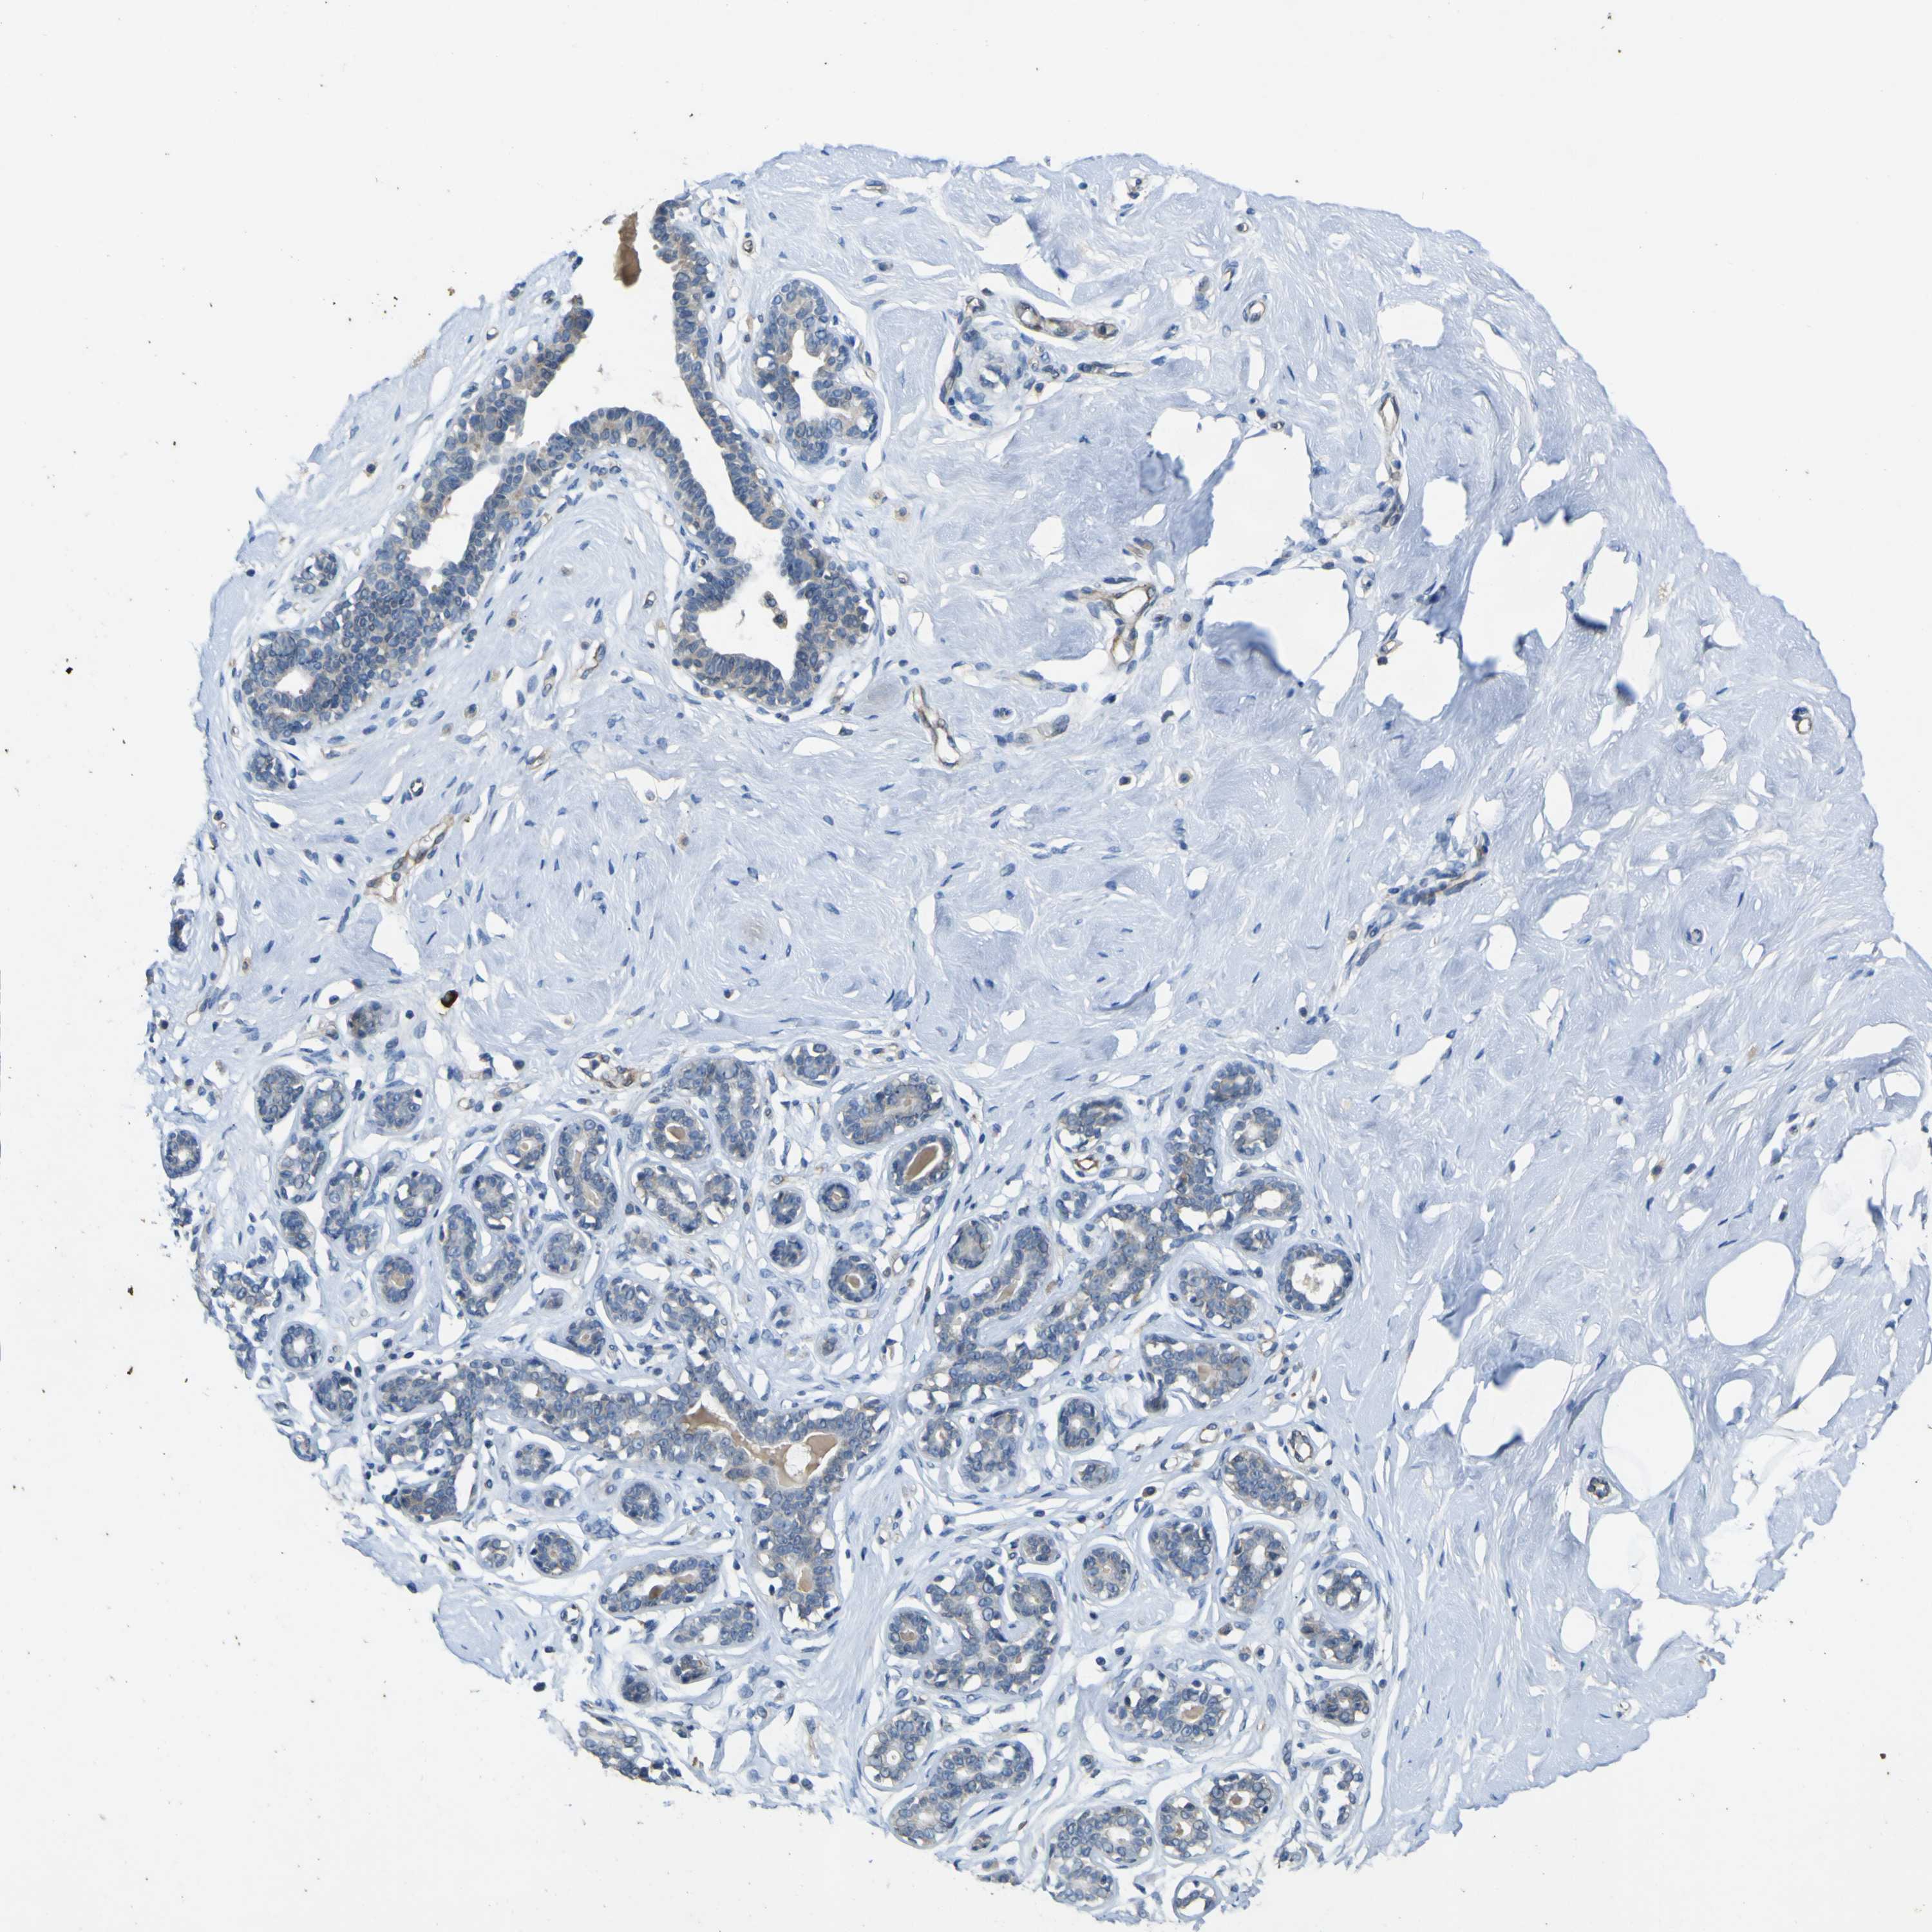

Tissue expression of LDLR Staining in pancreas The Human Protein Atlas Protein Atlas Ldlr  Correlation analysis based on mrna. The structure section provides predicted structures from the alphafold protein structure database and includes. Summary of ldlr expression in human tissue. Low density lipoprotein receptor (hgnc symbol) entrez gene summary: The pathology section contains mrna and protein expression data from 17 different forms of human cancer. Protein structure for human protein ldlr (ldlcq2) we use. Protein Atlas Ldlr.

From www.proteinatlas.org